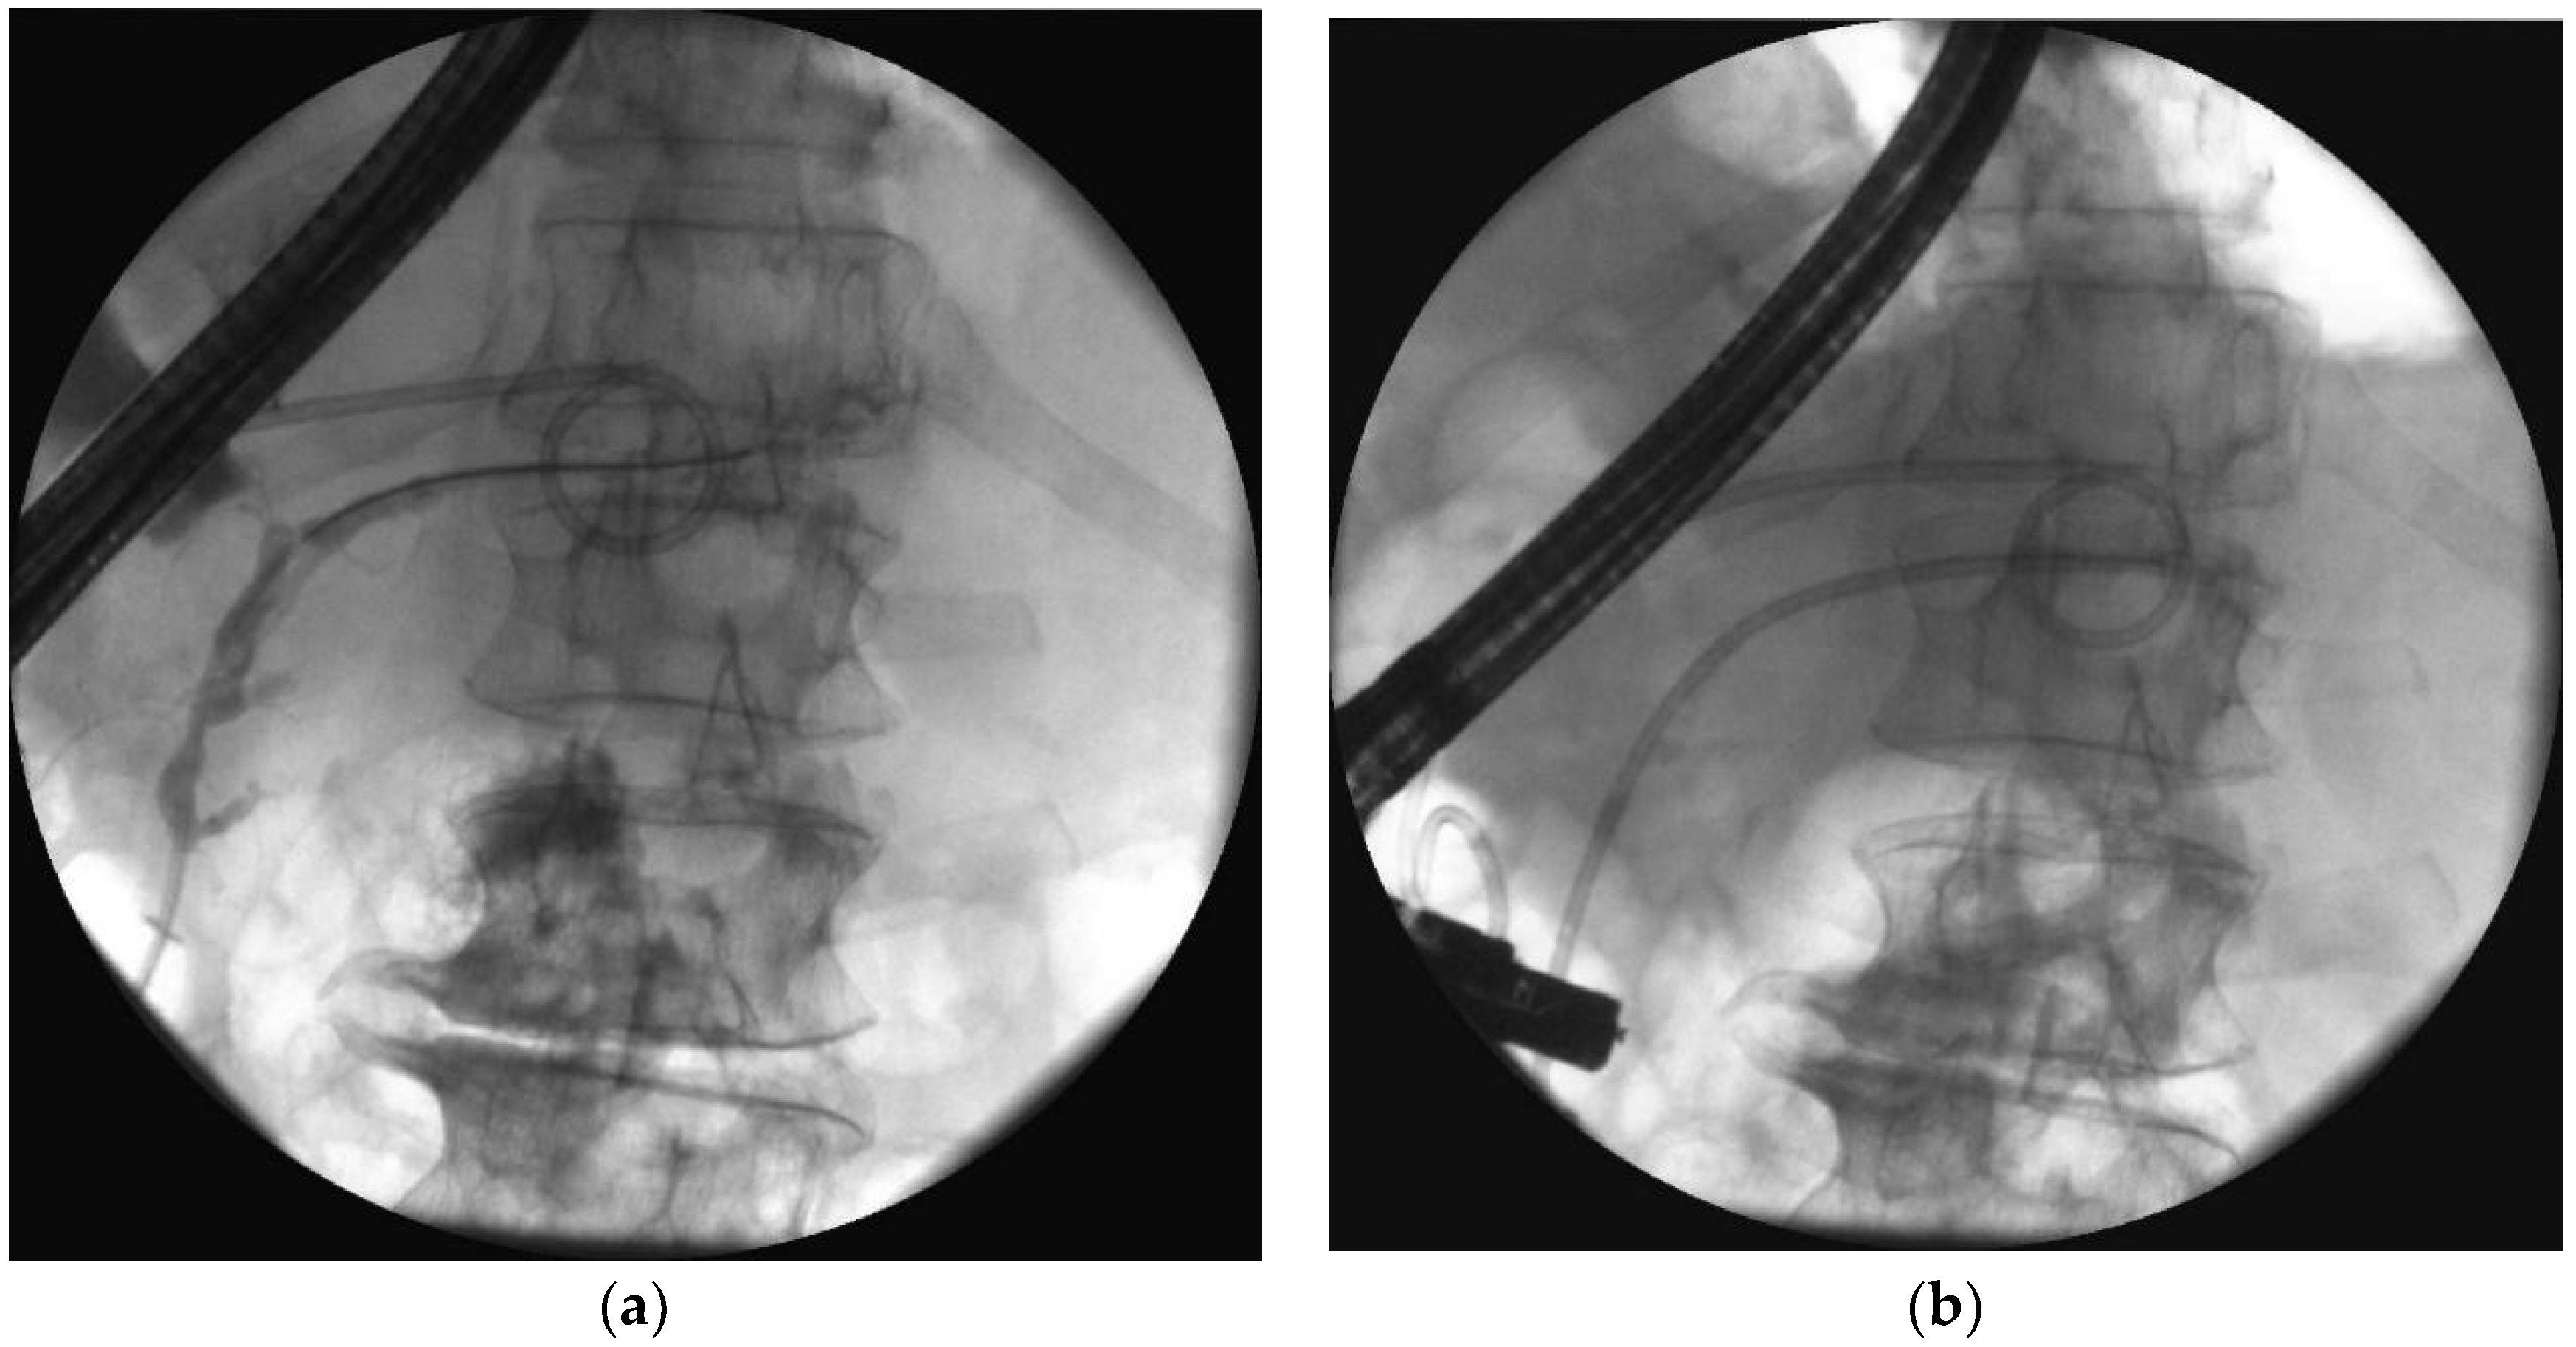

| Passive transpapillary drainage | The insertion endoscopic pancreatic stent to pancreatic duct through duodenal papilla. |

| Active transpapillary drainage | Endoscopic insertion pancreatic endoprosthesis as well as nasal drain to pancreatic duct through duodenal papilla. |

| Endoscopic necrosectomy under fluoroscopic guidance (endoscopic debridement) | Procedure that enable to remove necrotic tissues from necrotic cavity through transmural fistula under fluoroscopy with use of various types of endoscopic tools. Indication for endoscopic debridement is WOPN containing poorly-liquefied necrotic tissues. |